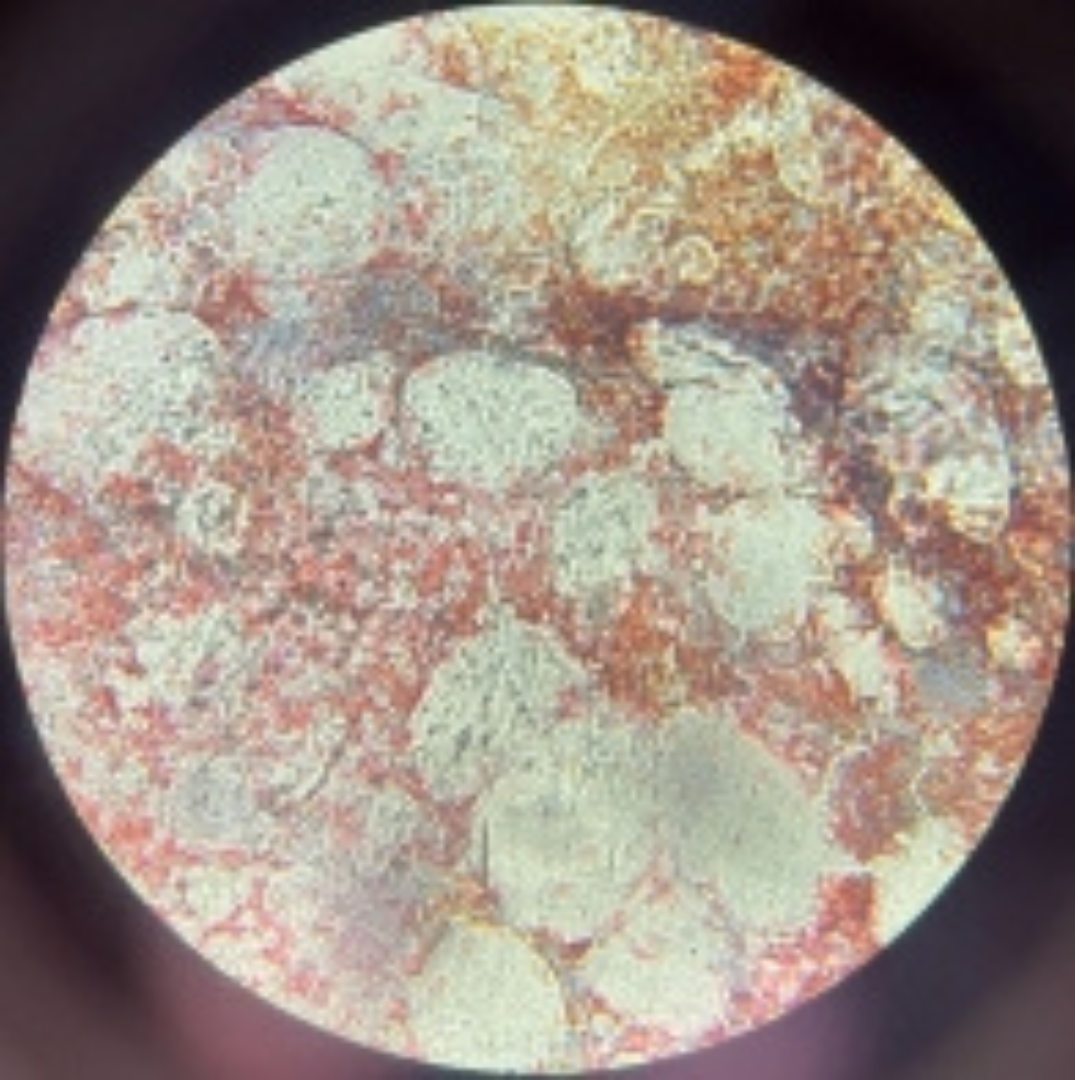

4

New cards

Blood

5

New cards

Bone Marrow

6

New cards

Bone Marrow

7

New cards

Bone Marrow